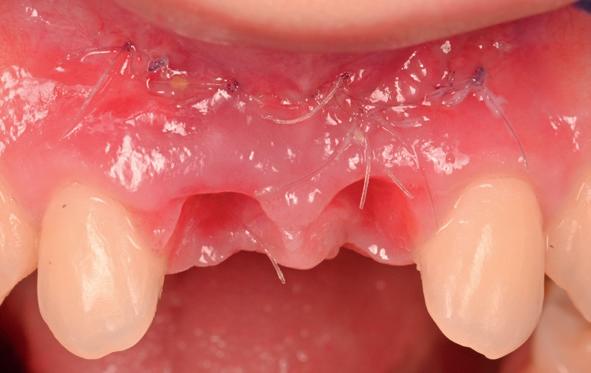

tinaal geslepen te worden als er geen 1,5 mm ruimte voor de vleugels behaald kan worden. De ruimte was op de dunste plekken 1 mm, dus een kleine preparatie in de 12 en 22 palatinaal was nodig. Omdat de kaak volledig afgevlakt was en dun was geworden, kunnen de dummies van de etsbrug enkel op de kaak “gelegd worden”, maar daarbij zijn er geen papillen en staat de cervicale rand van de dummies net voor de kaak. Een esthetisch resultaat kan daarmee niet behaald worden. Daarom is een aanvulling van de zachte weefsels in de breedte nodig, als het creëren van een emergence profile, waarbij het oogst alsof de gebitselementen uit het weefsel vertrekken.

pincisies met hechtingen naar het buccale en coronale deel getrokken en aldaar ingehecht. Met twee incisies werd ook de emergence profile gecreëerd (afbeelding 6-13). Voor een goede genezing van het

15. Twee weken post operatief

16. Creëren van een duidelijke indeuking in de mucosa voor emergence profile